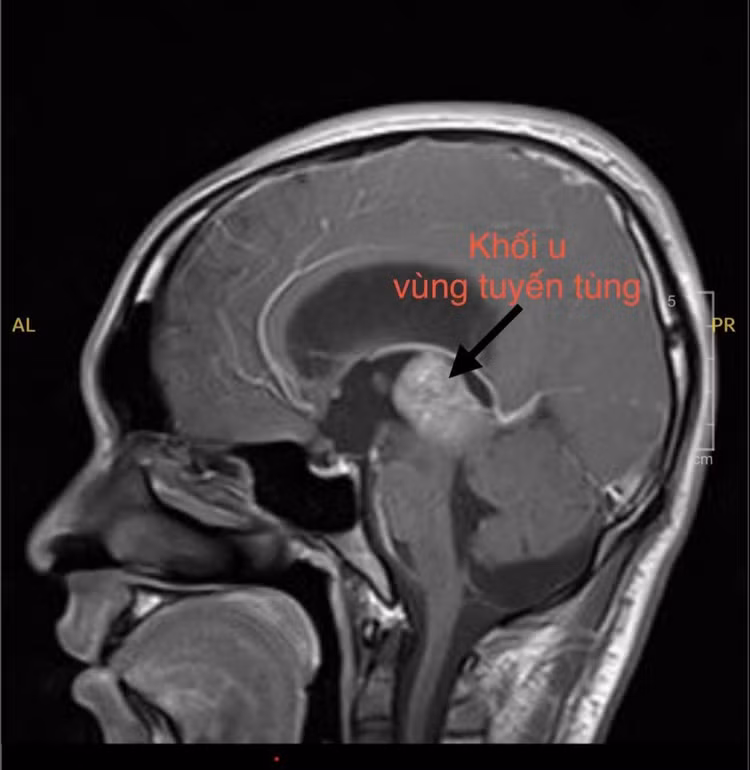

Hình ảnh MRI khối u vùng tuyến tùng. Ảnh BV

Tại đây, em được chỉ định chụp MRI não thì phát hiện có khối u vùng tuyến tùng – một dạng khối u nằm sâu giữa não, có thể gây chèn ép và cản trở đường lưu thông dịch não tủy. Đây chính là nguyên nhân khiến áp lực nội sọ tăng lên, gây ra những triệu chứng nặng nề mà em trải qua.

Theo bác sĩ, u vùng tuyến tùng là một khối u nằm ở vị trí sâu trong não, gần trung tâm não – một vị trí rất khó để sinh thiết cũng như can thiệp ngoại khoa. Với một bệnh nhân trẻ tuổi như H. và khối u nằm ở vị trí khó, việc lựa chọn hướng điều trị cho người bệnh là một thách thức lớn.